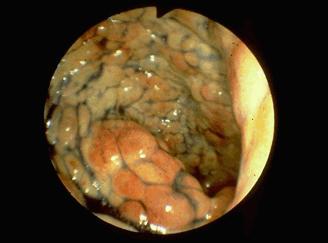

腸管のう胞性気腫症の内視鏡像     S状結腸部を色素を散布して、観察した色素内視鏡写真です。大小不同で、類円形の隆起が多発しております。隆起の表面は平滑で、発赤を伴っています。これらの所見より、隆起は粘膜下に主体をおく病変であることが分かります。

疾患(病理主体)の分類腫瘍様病変/腸管嚢胞性気腫症

部位(臓器別)大腸/S状

検査方法内視鏡

病変の最大径(ミリ)30〜34